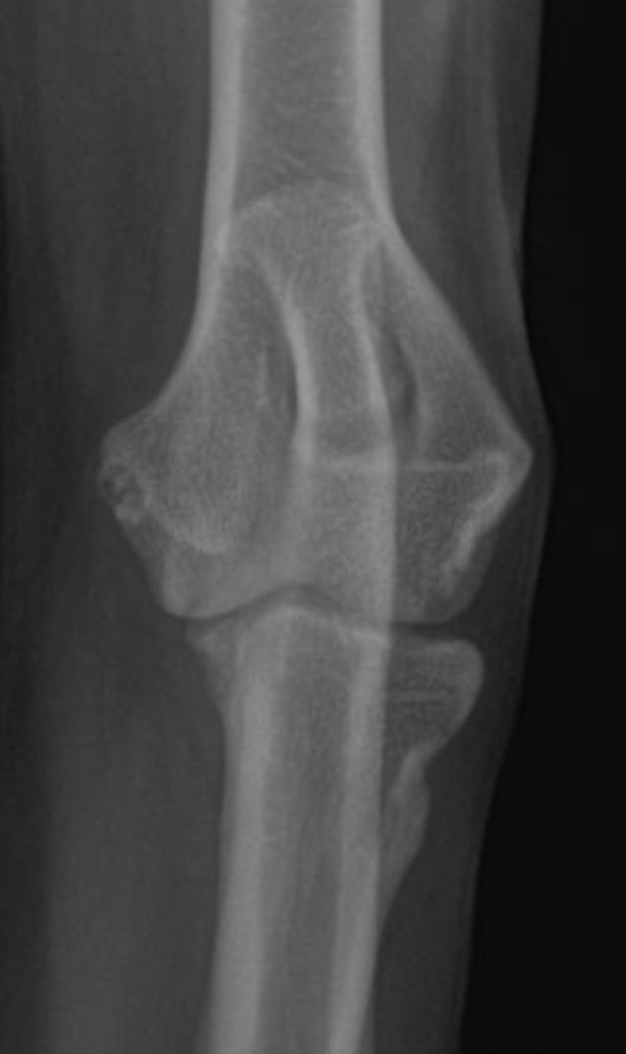

Humeral condylar fractures are one of the most common fore limb injuries in dogs. Prompt surgical repair is essential for the best long-term outcomes.

Humeral condylar fractures are breaks at the lower end of the humerus (upper fore limb bone) where it forms part of the elbow joint. This area has two rounded surfaces, or condyles — the medial and lateral — and the fracture can involve just one side (unicondylar) or split through both (bicondylar).

These injuries are relatively common in certain breeds and can occur even from low-impact events like falling or jumping down from furniture. Young dogs and breeds such as French Bulldogs are overrepresented. Spaniel breeds may also be affected due to

Humeral Intracondylar Fissure (HIF), where an incomplete fusion weakens the bone and predisposes it to fracture.

Dogs with humeral condylar fractures typically show sudden, severe limping after a fall or jump. The elbow is often very sensitive to touch, and the dog may hold the leg up and refuse to use it.

Diagnosis begins with an orthopedic exam. High-quality radiographs are essential. If the fracture is complex — particularly bicondylar fractures or suspected Humeral Intracondylar Fissure (HIF) — a CT scan may be recommended for a more complete view.

Prompt and accurate repair is critical. Surgery typically involves placement of a transcondylar screw to stabilize the fracture, often paired with plates or pins for additional support. Bicondylar fractures are especially challenging because the elbow is effectively split into three pieces, requiring meticulous reconstruction.

Humeral condylar fractures require surgeons with extensive experience and specialized tools. At AOCF, advanced imaging (CT and fluoroscopy) helps us understand the fracture before and during surgery. We maintain a full range of implants for even the most complex repairs and use minimally invasive techniques when appropriate. This approach ensures precise reconstruction, faster recovery, and the best possible long-term outcome for your pet.